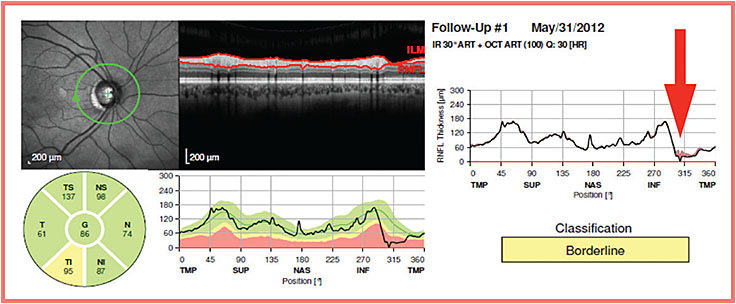

All four SD-OCT machines provide trend-based analysis of average and/or sector RNFL thickness. However, because of the localized nature of glaucoma progression, comparison of multiple RNFL thickness profiles obtained over time should be more sensitive in detecting subtle RNFL thickness changes (Figure 1, page 42).

Figure 1. Because of the localized nature of glaucoma progression, longitudinal comparison of RNFL thickness profiles should be more sensitive in detecting glaucoma progression than global or sectoral RNFL thickness analysis.